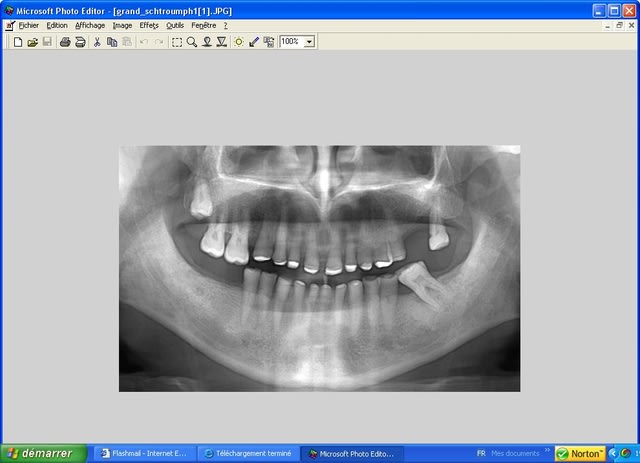

je m'étonne que tu ne trouves pas d'impacts d'attrition quand meme, on ne peut juger que sur tes photos mais l'usure me semble bien generale et harmonieuse, que la dentine fasse des cuvettes quoi de surprenant? que ces cuvettes ne moulent pas les antag ça peut s'expliquer par l'association d'autres causes

une érosion acide d'origine endogene est etonnante puisque localisée uniquement sur les faces occlusales, et aucune trace en faces buccales

une erosion acide d'origine exogene donnerait quand meme quelques traces en vest, il y en a tres peu

concernant le "stess" ocllusal éventuel, je ne vois pas de signes d'abfraction cervicale, meme si les mylolyses peuvent etre localisées ailleurs, c'est rarissime qu'on n'en trouve pas aux collets! mais c'est aussi dépendant du soutien paro, comment est il?

enfin concernant l'abrasion due au brossage c'est étonnant qu'il n'y ait pas de trace vest au moins sur les Pm maxillaires.

alors si pas d'erosion, pas d'abrasion, pas d'abfraction?

en fait il est possible qu'il y ait un peu de tout ça, le(s) probleme(s) etant plus anciens qu'aigus

rvg avant endo et 3 mois après endo retouche occlusale et rtr +prf on voit le "fut.." en 15 !

c'est le coté droit qui a été équipé en dernier c'est de ce coté que commence les problèmes cad fenestration en haut fracture dentaire en bas.